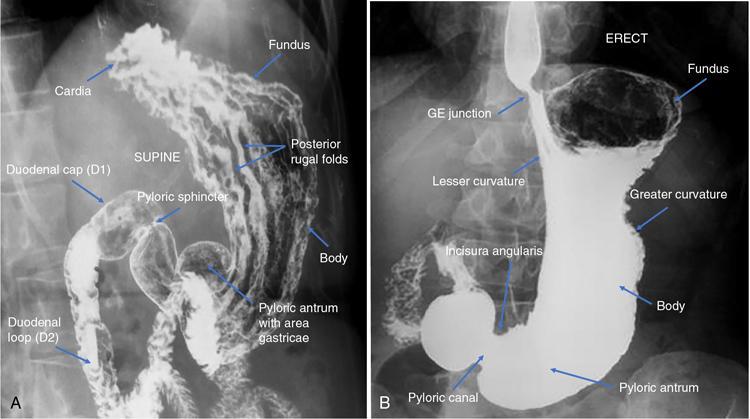

Swarup Nellore, Soumil Vyas, Ujwal Bhure, Ankit Jain, Richa Kothari, Daksh Mehta, Divya Kantesaria, Disha Lokhandwala, Karthik Ganesan The stomach is the most dilated portion of the gastrointestinal tract positioned between the oesophagus and the small intestine occupying the epigastrium, left hypochondrium and umbilical regions of the abdomen performing a multitude of functions including storage and mixing of food and controlling the passage of food into the intestine. Anatomically, the stomach is divided into the following parts (Fig. 8.2.1): the gastric cardia is the portion immediately adjoining the oesophageal opening into the stomach. The fundus is the dome-shaped part above the horizontal plane of the cardiac orifice which undergoes receptive relaxation and is the site of the autonomic pacemaker. The body is the largest part of the stomach extending from the cardiac orifice to the level of incisura angularis (notch like bend in the mid lesser curvature) containing majority of parietal cells (which secrete hydrochloric acid), chief cells (pepsinogen) and enterochromaffin-like cells (ECL). The pylorus is the tubular distal portion of the stomach which is further divided into the gastric antrum and pyloric canal. The pyloric antrum containing G-cells producing gastrin extends from the incisura angularis up to the pyloric sphincter which is an anatomical sphincter formed by concentric thickening of the circular muscle coat and encircles the narrow-slit like pyloric canal. The left dome of diaphragm and oesophagus lie superior to the stomach while the greater omentum and pancreas lie inferiorly. Spleen and liver lie on either side laterally while the transverse mesocolon is located inferolaterally. Diaphragm, greater omentum, left lobe of liver and anterior abdominal wall are anteriorly related to the stomach and contents of lesser sac including pancreas, spleen, splenic artery, transverse mesocolon, left kidney and adrenal gland lie posteriorly. The stomach is embryologically derived from the primitive foregut and is suspended anteriorly by the ventral mesogastrium and posteriorly by the dorsal mesogastrium. During development as the stomach rotates, the peritoneum grows and condenses to form perigastric ligaments, which contain blood vessels, lymphatics, lymph nodes, nerves and fat. The liver forms in the ventral mesogastrium, which develops into the falciform ligament, gastrohepatic ligament (GHL) and hepatoduodenal ligament (HDL). The spleen and pancreas form within the dorsal mesogastrium, which fuses with the posterior abdominal wall to form the gastrocolic ligament (GCL), gastrosplenic ligament (GSL) and splenorenal ligament (SRL). The perigastric ligaments are identified anatomically by the vessels contained in them (Fig. 8.2.2). The gastric cardia and lesser curvature of the stomach are attached to the inferior surface of liver by the lesser omentum by the gastrohepatic ligament respectively which contains the left and right gastric vessels. The inferior free edge of the gastrohepatic ligament extends inferiorly as the hepatoduodenal ligament between the porta hepatis and proximal duodenum gastrophrenic ligament extends between the stomach and the left hemidiaphragm. The gastrocolic ligament identified by the left and right gastroepiploic vessels, connects the greater curvature of the stomach to the anterior surface of the transverse colon. This ligament extends inferiorly as the greater omentum which is a double-layered peritoneum forming a drape anterior to the bowel loops. The gastrosplenic/lienogastric ligament bridges the posterolateral wall of the fundus and greater curvature along the proximal body of the stomach to the splenic hilum and contains the short gastric vessels. The gastrosplenic ligament is contiguous with the lienorenal ligament and both these structures constitute the lateral boundary of the lesser sac. Macroscopically the stomach shows a thick vascular mucosal lining in the form of longitudinal folds called gastric rugae. Microscopic layers of the stomach include mucosa, submucosa, muscularis externa and serosa. The mucosa includes surface mucus cells with simple columnar epithelium, gastric pits, gastric glands, lamina propria and muscularis mucosa. Submucosa includes connective tissue with submucosal Meissner’s plexus. Muscularis externa comprises three smooth muscle layers (longitudinal, circular and oblique) and Auerbach myenteric plexus. The outermost layer called serosa consists of loose connective tissue and visceral peritoneal lining. The arterial supply of stomach is constituted by the branches of celiac artery predominantly in the form of two anastomotic arcades along the lesser and greater curvature. Left gastric artery, a direct branch of the celiac trunk supplies the upper part of the lesser curvature while the lower part is supplied by the right gastric branch of the common hepatic artery arising at the upper border of pylorus. The left gastroepiploic artery, a branch of splenic artery, supplies the upper part of greater curvature and the inferior portion is supplied by the right gastroepiploic artery which is a branch of the gastroduodenal artery. The fundus additionally receives few small short gastric branches from the splenic artery. The veins follow the arteries in their nomenclature. Left and right gastric vein show direct drainage into the portal vein. The splenic vein derives flow from the short gastric and left gastroepiploic vein whereas the right gastroepiploic vein drains into the superior mesenteric vein. Pylorus can be surgically delineated by the prepyloric vein of Mayo lying on its anterior surface. Intrinsic nerve supply consists of the myenteric plexus of Auerbach and submucosal plexus of Meissner. Extrinsic nerve supply consists of sympathetic and parasympathetic components. Sympathetic nerve supply arises from T5 to T9 spinal cord segments supplying the celiac plexus via the greater splanchnic nerve. The plexuses then travel along the respective branches of celiac artery supplying the stomach. Parasympathetic nerve supply is derived from oesophageal plexus of vagus dividing into two vagal trunks. Right (posterior) vagus gives off the posterior gastric branch also called the criminal nerve of Grassi supplying the cardia and fundus of stomach. Right vagus then gives off a celiac branch and continues along lesser curvature of stomach as the posterior gastric nerve of Latarjet supplying the antrum, body and pylorus. Left (anterior) vagus gives off a hepatic branch then continues along the lesser curvature as the anterior nerve of Latarjet supplying the antrum, body and pylorus. Crow’s feet innervation to antropyloric area are important surgical landmarks preserved during highly selective vagotomy receiving branches from both major nerve trunks (anterior and posterior) at the incisura angularis. Anatomical lymphatic drainage is divided into three areas. Area I is the superior two-thirds of stomach draining via the nodes along left and right gastric vessels into the aortic nodes. Area II includes the right two-thirds of the inferior one-third which drains through the nodes along right gastroepiploic vessels via the subpyloric nodes into aortic nodes. Area III includes left one-third of greater curvature draining via short gastric and splenic nodes into suprapancreatic nodes and ultimately into aortic nodes. Gastric lymph node stations are divided into 4 levels with 16 lymph node stations: Paraesophageal nodes below the diaphragmatic hiatus (17) and above the diaphragmatic hiatus (18) are also included. The stomach first appears as a fusiform dilatation in the distal endodermal foregut in the 4th week of embryonic life. The dorsal and ventral mesogastrium suspend the developing stomach to the respective abdominal walls. Preferential growth along the dorsal border of the developing stomach leads to the formation of a convex dorsal border (greater curvature) and a concave ventral border (lesser curvature). The stomach subsequently undergoes a sequence of rotations. The first (90 degrees) clockwise rotation occurs around the longitudinal axis which brings the lesser curvature to the right and greater to the left. This rotation also brings the dorsal mesogastrium towards the left and ventral to the right creating a space behind the stomach called as the lesser sac or omental bursa. The second clockwise rotation occurs around the anteroposterior axis, with the caudal or pyloric part moving upwards and to the right while the cephalic or cardiac portion moves towards the left and slightly downward causing the stomach to assume its final anatomic position. This rotation causes the dorsal mesogastrium to bulge downwards and grow further to eventually become a double-layer apron called the greater omentum. The developing liver divides the ventral mesogastrium into the falciform ligament extending from the ventral abdominal wall to the liver with its lower free edge forming the ligamentum teres, the visceral peritoneum surrounding the liver and the lesser omentum with its two parts – the hepatogastric ligament and hepatoduodenal ligament. The dorsal mesogastrium gives rise to the redundant greater omentum, gastrocolic ligament, gastrosplenic ligament and lienorenal ligament. These perigastric ligaments help us in deciphering patterns of the spread of gastric malignancies and in taking decisions regarding their management and prognostication. These will be further explained in detail under the section of gastric malignancies. An abdominal radiograph is often the initial imaging test for evaluation of acute abdominal pain. The gastric bubble is seen below the left hemidiaphragm in situs solitus. Presence of gastric outlet obstruction may show a distended stomach with gasless small bowel. Hollow visceral perforation is diagnosed by free air seen under domes of diaphragm. Also, the presence and position of various tubes like the nasogastric tube can be confirmed using a radiograph. A fluoroscopic upper gastrointestinal (GI) examination is the radiological study of oesophagus, gastro-oesophageal junction, stomach, duodenum up to duodenojejunal junction by oral administration of contrast. Barium sulphate is a good contrast medium for GI studies as it is radio-opaque, non-absorbable, inert to tissues and can be used for double-contrast studies. Patient should be nil by mouth at least 4 hours prior to the examination. In a single contrast examination, the emphasis is on mucosal relief, luminal distention with contrast material and compression. In the erect position, a small amount of contrast is given to swallow while the oesophagus is visualized under fluoroscopy. The table is then made horizontal and the patient is rotated in a clockwise manner as seen from the foot end of the patient, thus ensuring good coating of the stomach mucosa. Mucosal relief images are then obtained in supine and prone positions to demonstrate the mucosal fold pattern and possible filling defects. After giving some more contrast, the patient is turned oblique with the right side dependent and spot images of the duodenal cap and C loop are taken both in distended and empty states. The patient is again positioned erect and more images of duodenal cap and loop are taken. Further contrast is given to optimally distend the lumen and assess for possible contour abnormalities, wall rigidity and strictures. Compression techniques help assess for filling defects and lesions, in the compressible areas of the stomach. Images are taken in multiple positions – supine, prone, right anterior oblique, right lateral, left posterior oblique in recumbent and right anterior oblique in erect position. Gastric peristalsis and emptying can be observed at fluoroscopy. Advantages of the single contrast technique are that it can be performed quickly, well-tolerated and requires less patient cooperation as compared to double-contrast studies. It can even be performed in physically debilitated patients. Barium is contraindicated in suspected cases of perforation, aspiration, fistula or recent GI biopsy. Single contrast examination can be performed using water-soluble iodinated contrast media in these cases and immediate postoperative patients. Earlier, ionic contrast like Gastrograffin was used. However, due to its high osmolarity, nowadays, non-ionic contrast is preferred as it causes less electrolyte imbalance due to its low osmolarity. Also, it delineates the GI tract very well due to less dilution. Double-contrast studies provide better evaluation of the mucosa than do single-contrast studies. Here, the emphasis is on coating the mucosa with barium and distending the lumen with gas. A well-performed double-contrast study is biphasic and also incorporates some single-contrast techniques. The initial part of the examination is the same as a single contrast examination to obtain the mucosal relief images. Then, gas-forming powder that produces carbon dioxide within the stomach lumen is given with more barium. With the double-contrast technique, the mucosa is coated with a high-density barium suspension and the lumen distended with gas. The patient is rotated in a clockwise manner as seen from the foot end of the patient, thus ensuring good coating of the stomach mucosa. Spot images of the distended stomach are taken followed by the duodenal cap and loop in oblique right-side dependent position. Patient is brought back to erect position erect and more images of stomach, duodenal cap and loop are taken. Further contrast is given to distend the lumen. Residual fluid or food debris in the stomach impairs stomach coating, and lack of adequate coating may preclude visualization of lesions. In addition, optimal gaseous distention is important as underdistention will cause a false appearance of abnormally thickened, and overdistention can obliterate abnormal folds. With normal gastric anatomy, the gastric fundus is best visualized in the upright left-posterior-oblique position, the body in the supine anteroposterior position and the antral-pyloric region in the supine left-posterior-oblique position. The normal gastric mucosal surface should be smooth on double-contrast studies. Areae gastricae appear as reticular networks of polygonal tufts which, owing to the presence of barium in the narrow intervening grooves, are coated with white lines. These are seen most often in the antrum or body of the stomach but can also be seen in the fundus. Areae gastricae are identified on double-contrast studies in 70% of patients and are seen more often in elderly patients. Polygonal tufts should normally range in size from 2 to 3 mm in the antrum and 3 to 5 mm in the body and fundus. Normal gastric folds are more prominent in the proximal to mid stomach and more undulating along the greater curvature as compared with the lesser curvature. Antral folds should be typically effaced with the double-contrast technique. Gastric cardia is characterized by three or four stellate folds radiating from a central point at the gastro-oesophageal junction; this is known as the cardiac rosette and is best visualized in the supine right-lateral position. Ultrasonography (USG) is the modality of choice to visualize hypertrophic pyloric stenosis in infants. Although USG does not play much of a role in adults for imaging of stomach due to reflection of sound waves by air, luminal distension with water may enable to identify mucosal – submucosal pathologies and to assess perigastric relationships in pathologies. CT can not only evaluate the location and anatomy of the stomach, but also provide additional information about the relationship of the stomach to surrounding structures. An optimal CT examination of the stomach includes good stomach distension with a well-visualized wall. Gastric distention can be achieved by the oral administration of negative or positive luminal contrast. Positive contrast agents include a 1%–2% barium suspension or a 2%–3% solution of a water-soluble iodinated contrast agent. Water-soluble agents should be used in cases of suspected perforation. Positive agents provide a bright lumen with better identification of luminal encroachment or diverticula but may limit detailed evaluation of gastric wall enhancement. Positive contrast also may not mix well with gastric contents, producing a pseudotumor appearance. On the other hand, neutral or negative contrasts agents, usually water, produce a low attenuation lumen which allows for more detailed evaluation of the gastric wall and its enhancement pattern following intravenous contrast and is preferred for three-dimensional imaging. Multidetector CT with thin collimation allows for postprocessing in any orthogonal plane. The CT data of the stomach can be manipulated to simulate endoscopic images (virtual gastroscopy). This display technique accentuates the stomach wall and folds. Prior to evaluating the stomach with CT, oral contrast is administered at repeated intervals as well as immediately prior to scanning. Multiphasic scanning after intravenous contrast may be employed at 25–35 seconds (late arterial), 55–75 seconds (venous phase) after contrast injection. Normally, the gastric wall may enhance to approximately 120 Hounsfield Units after intravenous contrast administration. The mucosa may enhance more than the relatively lower-attenuation muscularis propria. Abnormal enhancement of the wall can highlight pathologic processes. The CT appearance of the stomach also depends upon the degree of distention. When well distended, the body and fundus is less than 5 mm thick, though the normal antrum may appear slightly thicker. The presence and pattern of wall enhancement, degree and location of wall thickening, and length of an involved segment may be assessed. Comprehensive MRI examination of the stomach and duodenum by the combined use of T2-weighted single-shot and T1-weighted gradient echo (GRE) – with and without fat suppression, and gadolinium-enhanced 3D GRE helps to detect the spectrum of gastric diseases on MRI. These sequences minimize artefacts from bowel peristalsis, increase the sensitivity of detection of peritoneal and serosal disease by suppressing the high signal of intra-abdominal fat, widen the dynamic range of abdominal tissue signal intensities and distinguish between intraluminal bowel contents and bowel wall. The gastric rugae are well seen on T2-weighted single-shot spin-echo images and their enhancement appears as bands of enhancing tissue arranged perpendicular to the external contour of the gastric wall. The normal gastric wall enhances more intensely than other segments of bowel on immediate postgadolinium SGE images. Water is frequently used as an oral contrast agent when imaging the upper GI segment-stomach and duodenum. Noninvasive dynamic study for assessment of gastric motor function and wall motility can also be done using MRI for diagnosis of gastroparesis. Gastric emptying scintigraphy (GES) is a well-established radionuclide procedure to evaluate patients with suspected gastric motility disorder, more so for non-invasive assessment of gastroparesis in patients with symptoms of postprandial fullness, nausea, vomiting, abdominal pain, bloating, early satiety, loss of appetite, as well as weight loss. Gastroparesis, commonly seen in diabetics, is a condition that affects the normal spontaneous movement of the gastric muscles, leading to impairment of gastric motility, because of which the stomach cannot empty itself of food in a normal fashion and time. GES can also provide useful information with regards to assessment of impaired gastric motility in patients with GERD (gastro-oesophageal reflux disease) unresponsive to routine therapy, diabetics with poor glycemic control, and also in patients with colonic inertia who are being considered for colectomy (since benefits of colectomy are mitigated in patients with concurrent impaired gastric emptying). On the other hand, GES is also useful for assessment of rapid gastric emptying (GE), which is a major factor in dumping syndrome, often seen post peptic ulcer surgery, with or without vagotomy. The solid or liquid component of a meal is radiolabelled with a radiopharmaceutical, which is consumed by the patient and subsequently measured gastric radioactive counts by scintigraphy correlate with the volume of the meal remaining in the stomach. Solid-phase GES is used for the evaluation of gastric motility disorder/gastroparesis. Liquid-phase gastric emptying is generally not clinically useful since it is often in the normal range in spite of deranged emptying for solids even with severe gastroparesis. The preferred radionuclide meal for the gastric emptying scintigraphy includes egg-white radiolabelled with 0.5–1.0 mCi of Technetium-99m (99mTc) [approximate caloric value of 255 kcal]. Two large eggs (egg-whites), two slices of bread, fruit jam, water (120 mL approximately), and the radiopharmaceutical (0.5–1.0 mCi of 99mTc–sulphur colloid). For patients allergic, to eggs, alternative meals like oatmeal or Liquid Ensure nutrient supplement can be used. Reporting should include the percentage of radiotracer retained in the stomach at defined time intervals. The normal reference values for comparison are as follows: Grading the severity of the delay in gastric emptying based on gastric retention at 4 hours of the study: Gastro-oesophageal reflux (GER) is a common condition in infants and children, wherein there is reflux of stomach contents into the oesophagus, due to possible incompetence of gastro-oesophageal sphincter, which can lead to development of symptoms like regurgitation, heartburn, cough and dyspepsia. Children can present with recurrent respiratory infections, iron deficiency anaemia and failure to thrive. It is often a self-limited process in infants and children which usually resolves by 12–18 months of age. On the other hand, gastro-oesophageal reflux disease (GERD) is a chronic pathological process which can be troublesome. Scintigraphic evaluation of gastro-oesophageal reflux, popularly known as ‘milk scan’, is an established imaging modality and has sensitivity of 75%–100%. This radionuclide test for gastro-oesophageal reflux is physiological and quantitative and commonly used for diagnosis in neonates and infants. Four hours fasting is preferred. A liquid meal consisting of formula, milk, or orange juice mixed with the radiopharmaceutical is administered either orally or by nasogastric tube. 99mTc–sulphur colloid. Dose: 0.2 to 1 mCi. After administering the liquid meal and allowing burping, the baby is positioned supine under the gamma camera detector head, including chest and upper abdomen in the field of view. A radioactive marker can be placed at the mouth. Anterior serial dynamic planar images are acquired for around 60 minutes with a framing rate of 5–10 seconds per frame. Delayed anterior static image of the chest may be acquired additionally. The acquired frames are reviewed in cinematic display for visual estimation and to look for reflux of the radiotracer into the oesophagus. Reflux is seen as distinct spikes of radiotracer activity into the oesophagus. For quantitative estimation, the volume of each episode of reflux, frequency of episodes and rate of reflux clearance from the oesophagus are taken into consideration. Percentage of reflux is calculated by drawing an ROI over the oesophageal spike of radiotracer activity and the counts are calculated and expressed as a fraction of the gastric activity counts. Values greater than 5% are suggestive of reflux. Semiquantitative evaluation grades each reflux event: Based on this, four categories can be formulated: The greater the number of high-level reflux events and the longer they last, more severe is the gravity of the problem. Pulmonary aspiration should also be looked for, though the sensitivity of detection is poor. Liquid gastric emptying can be evaluated during the same study up to 2 hours. Normal values for liquid gastric emptying are: Endoscopy is the preferred examination to evaluate for majority of the upper GI symptoms. It is very sensitive in detecting mucosal lesions and simultaneously, biopsies can be taken. In cases of upper GI bleed, endoscopy can not only detect the site and cause of the bleed, but also further treatment like adrenaline/sclerosant injection or ligation can be done. EUS can provide detailed assessment of the 5 layers of the gastric wall and is thought to be the most accurate non-surgical method for local tumour staging (Fig. 8.2.9). For subepithelial (submucosal) gastric lesions, EUS can assess the echogenicity of a lesion, the exact layer of the gastric wall which is involved (accurate T-staging of a tumour) and assess for the presence of blood flow with Doppler ultrasound to help ascertain the likely aetiology. EUS-guided fine needle aspiration may also provide additional diagnostic information. Hiatus hernia is a common positional abnormality of stomach, characterized by herniation of abdominal contents, commonly the gastro-oesophageal junction and stomach, into the mediastinum above the diaphragm through a widened oesophageal hiatus. The oesophageal hiatus is an elliptical opening with complex anatomy formed by the right and left crus of the diaphragm. However, the most common anatomical description is of the right crus splitting into two bundles, the right and left, which form a sling encircling the distal oesophagus and may be reinforced by the left diaphragmatic crus. The distal oesophagus is typically anchored to the oesophageal hiatus by a main restraining structure which is the phrenicoesophageal ligament/membrane (the fascia of Laimer) which is a condensation of endo-thoracic and endo-abdominal fascia and this membrane circumferentially inserts into the oesophageal musculature in close proximity to the squamocolumnar junction (SCJ). The ligament maintains the competence of the oesophageal hiatus and prevents rostral herniation of the gastro-oesophageal junction and stomach. During normal physiological swallowing, the longitudinal layer of the oesophageal muscularis propria contracts with associated oesophageal shortening and stretching of the phrenicoesophageal ligament/membrane resulting in the transient elevation of the oesophagogastric junction and portion of the stomach above the hiatus. At the end of the swallowing mechanism, the elastic recoiling of the phrenicoesophageal ligament/membrane restores the migrated segment to its normal position. With ageing-related wear and tear, the ligament becomes lax with progressive depletion of elastin fibres resulting in proximal migration of the gastro-oesophageal junction and stomach. Other potential risk factors of fibromuscular degeneration are caused by increase in the intra-abdominal pressure as occurs in obesity and pregnancy. The majority of the symptomatic cases of hiatal hernia present with the clinical symptoms of gastro-oesophageal reflux disease (GERD) with most characteristic manifestations of acid regurgitation, heartburn, dysphagia, epigastric or chest pain and even chronic iron deficiency anaemia. Large hernias may also present with early satiety. Conventionally, hiatus hernias are classified into sliding and paraesophageal varieties. The current comprehensive anatomic classification has evolved to include a categorization of hiatal hernias into Types I–IV and is necessary especially regarding the treatment approach, as indications for the surgical method are quite different between sliding and paraesophageal hernias. Majority of hiatus hernias (95%) are sliding hiatus hernias (type I), the remaining type II–IV hernias as a group are referred to as paraesophageal hernias (PEH), with more than 90% of these comprising type III, and the least common being of type II. The assessment of hiatus hernia can be done by various modalities including radiological, manometry and endoscopy studies. The diagnosis of a large hiatus hernia is straightforward, however, identifying a small one is challenging due to mobility of the gastro-oesophageal junction during physiological process like deglutition and respiration. According to the SAGES Guidelines, only those investigations which will alter the clinical management of the patient should be performed. Radiological investigations are usually indicated for diagnosis and presurgical evaluation. Plain chest radiographs demonstrate opacity within the chest typically in the midline overlapping the cardiac shadow or paramedian location (Fig. 8.2.14A), with or without an air-fluid level. Barium swallow radiography is still considered an easy tool for diagnosis of hiatus hernia and provides essential information about the size, location, motility dysfunction, stricture secondary to GERD and stenosis. The evaluation of hiatus hernia requires understanding of anatomical radiographic landmarks like phrenic ampulla, A ring and B ring (or Schatzki’s ring) on a barium study (Fig. 8.2.14B). The phrenic ampulla is a globular structure seen above the diaphragm and below the tubular oesophagus during a contrast swallow. The A ring represents a muscular ring visible at the upper margin of the phrenic ampulla and physiologically corresponds to the highest-pressure zone within the lower oesophageal sphincter, this is often seen as a transient indentation on the oesophageal lumen. The B ring identified in about 15% of individuals, representing the mucosal ring corresponds to the squamocolumnar junction (Z line) and divides the phrenic ampulla into the oesophageal vestibule (A ring to B ring) and the sliding hiatus hernia (B ring to the stomach below the diaphragm). The B ring is a persistent constriction which is not usually not more than 2–3 mm and despite mucosal, can sometimes be symptomatic and require dilatation. By convention, there must be a distance of 2 cm or more between the B ring and the hiatus, to call it a hiatus hernia as physiological migration up to 2 cm is known in normal individuals. Although not reliable, barium studies may also provide information about a short oesophagus, which is identified as a tubular straightened oesophagus with the oesophagogastric junction fixed far above the diaphragm and may be stenotic, the intrathoracic herniated stomach revealing a more elongated funnel/bell – shaped configuration. Cine fluoroscopy provides further additional information about the bolus transit through gastro-oesophageal junction. The major drawbacks of the procedure are non-visualization of B-ring in majority of the cases, radiation exposure, barium/iodine hypersensitivity, contraindication in pregnancy and increase risk of aspiration in paraesophageal hernia causing pneumonitis. Computed tomography (CT) scan is not routinely advised for the primary diagnosis of hiatus hernia but is indicated in cases of suspected complications like volvulus in paraesophageal hernia, obstruction, perforation and strangulation. Multi-slice CT with reconstruction in sagittal, coronal planes and 3D reformations have increased the sensitivity of CT in detection of hiatal hernia. Oesophagogastroduodenoscopy gives added advantage of real-time visual assessment of the mucosa of the oesophagus, stomach and duodenum. The common diagnostic criteria in endoscopic is proximal migration of gastro-oesophageal junction by >2 cm. Endoscopy can also determine the presence of erosive esophagitis or Barrett’s oesophagus. Further, the inability or difficulty of negotiating the scope into duodenum in the presence of a large hiatal hernia is diagnostic of paraesophageal hernia with volvulus. Evaluation of gastric viability is also important in patients undergoing emergency surgery for incarcerated hernias. The disadvantage of the procedure is lack of reproducibility; retching or belching of the patients during examination which can alter the location and anatomy of GEJ and excess air insufflation of the stomach which may exaggerate the size of the hernia. Oesophageal manometry is measured at the level of the diaphragmatic crura, however, manometric landmarks differ from that of barium study and endoscopy, and identified by pressure inversion point. In patients with a paraesophageal hiatal hernia, placement of the manometry catheter across the lower oesophageal sphincter and below the diaphragm can be difficult. The procedure is planned before surgery to exclude motility disorders like achalasia and to verify the integrity of oesophageal peristalsis. pH testing is not essential in the diagnosis of a hiatal hernia, but is necessary for a quantitative analysis of reflux in a case of hernia which can be relieved by antireflux surgery. Confirmation of abnormal gastro-oesophageal reflux on upper endoscopy, or increased oesophageal acid exposure on pH monitoring is necessary prior to operative intervention in patients with a sliding hiatal hernia. Nuclear medicine studies, transoesophageal echocardiogram (TEE) and endoscopic ultrasound (EUS) can also demonstrate hiatal hernias but are not routinely used for diagnosis. The main aim of treatment in symptomatic patient is to reduce the acid reflux. Lifestyle modifications are the first line of management and include weight loss, elevating the head of the bed preferably by 8 inches during sleep, avoidance of meals for atleast 2–3 hours before bedtime and elimination of ‘trigger’ foods. According to the SAGES Guidelines updated in April 2013, the treatment protocols are provided on the basis of types of the hiatus hernia. Type I (sliding) hiatus hernia are usually managed with proton pump inhibitors for 8 weeks, once or twice daily depending on the symptoms. Other alternatives are H2 receptor antagonists and antacids. If the patient is not relieved symptomatically by medication, surgical repair like laparoscopic fundoplication (Nissen or Toupet) can be done. Steps of fundoplication comprise surgically relocating the gastro-oesophageal junction below the diaphragm, maintaining an oesophagogastric angle to prevent gastro-oesophageal reflux, constructing a gastric wrap around the distal oesophagus to support the distal oesophageal sphincter and increase its resting pressure, and finally approximate the diaphragmatic hernia to narrow the widened hiatus. In all symptomatic Type II, III and IV hiatus hernia, surgical repair is strongly recommended as the primary treatment, particularly those with acute obstructive symptoms or which have undergone volvulus. Routine elective repair of completely asymptomatic paraesophageal hernias may not always be indicated and determinants for surgery should include the patient’s age and co-morbidities. These fundoplication surgeries are described later in the text. Gastric volvulus is an uncommon entity and characterized by abnormal rotation of the stomach (usually >180°) along the long or short axis, leading to variable degree of gastric obstruction, which can be of a closed-loop type resulting in strangulation. The exact incidence of gastric volvulus is unclear as patients with a chronic presentation may never be diagnosed.2 Approximately, 10%–20% cases of gastric volvulus occur in children less than 1 year, while the other 80% cases are detected in adults, of which 80%–90% are often encountered in the fifth decade of life.3 No significant predilection is seen with either sex or races. Gastric volvulus can be classified on the basis of aetiology, axis of rotation and duration of onset. While classification based on axis of rotation by Singleton is widely accepted and more relevant to the radiologist, classification based on duration of onset of symptoms is more relevant in clinical assessment. On the basis of axis of rotation (Fig. 8.2.15), gastric volvulus is divided into organoaxial volvulus, mesenteroaxial volvulus and the rarest combined/mixed type. Organo-axial volvulus, by far, the most common type of gastric volvulus, encountered often in the elderly, is characterized by rotation of the stomach along its long axis, that is, cardio-pyloric axis, and resulting in an ‘inverted stomach’ with a horizontal orientation, in the form of anterosuperior displacement of the antrum and posteroinferior rotation of the fundus, so that the greater curvature is displaced superiorly and lesser curvature caudally in the abdomen (Fig. 8.2.16). The site of obstruction in this type of volvulus is at the cardia or at pylorus. It has a higher predisposition towards strangulation and ischaemia. Organo-axial volvulus also shows association with the paraoesophageal hernia or diaphragmatic defects, which allows abnormal movement of the stomach along the long axis. If the degree of rotation is less than 180 degrees, the patient may have an incomplete or partial volvulus which is not completely obstructing and may be asymptomatic; it may be more appropriate to describe it as organo-axial position rather than volvulus. Mesenteroaxial volvulus is less commonly encountered (30%) and accounts for about 29% of cases, is reported more often in young adults or children. It occurs when the stomach rotates around its short (transverse) axis, that is, line connecting the midpoint between the lesser curvature and the greater curvature of the stomach, leading to a vertically oriented stomach, with anterior rotation of the pylorus, antrum and resultant displacement of the antrum above the gastro-oesophageal junction (Figs 8.2.17 and 8.2.18). The site of obstruction is usually at antropyloric region. It is usually not associated with a diaphragmatic defect and is often idiopathic. The third and rarest type of gastric volvulus is the combined type when the stomach shows both rotation along the short and long axes. Based on aetiology of rotation, gastric volvulus can be subdivided into either primary or secondary. Primary gastric volvulus representing 25%–30% of the cases, is more common in the adults. It occurs in the subdiaphragmatic location due to abnormality in the gastric fixation, exclusively because of disruption, laxity or absence of the gastric ligaments which anchor the stomach in place. These ligaments namely the gastrohepatic, gastrocolic, gastrophrenic, gastrosplenic and gastropancreatic ligaments, along with gastro-oesophageal junction and pylorus, provide anchorage and fix the stomach in place intra-abdominally, and prevent abnormal rotation of the mesentery. The primary gastric volvulus usually presents with the mesenteroaxial type of anatomical configuration. Around 70% of patients present with secondary gastric volvulus occurring due to abnormal rotation around the lead point formed by associated disease. The most common association of gastric volvulus is seen with paraoesophageal hiatus hernia. Other causative factors of volvulus include congenital or traumatic diaphragmatic hernia, diaphragmatic paralysis, eventration, connective tissue disorders, previous surgery, adhesions, peptic ulcer, neoplasm, splenomegaly or absence of the spleen and colonic overdistension. On basis of clinical presentation and speed of onset, gastric volvulus can be acute, subacute or chronic. Acute gastric volvulus is a surgical emergency and usually presents with sudden onset epigastric pain, distension, non-bilious vomiting or severe retching, depending on the degree of obstruction. The Borchardt triad of acute volvulus comprises severe epigastric pain and distention, retching but inability to vomit, and difficulty or impossibility of passing a nasogastric tube and may be observed in 70% of cases. Other symptoms include hematemesis due to mucosal sloughing in stomach gangrene or mucosal tear due to retching, dysphagia and dyspnea. Even after prompt treatment, mortality of acute gastric volvulus can be up to 30%–50%, likely secondary to gastric ischaemia, perforation or necrosis resulting from severe gastric obstruction (closed-loop obstruction) causing vascular compromise, making it a life-threatening surgical emergency. Chronic gastric volvulus represents spectrum of diseases from long-standing partially obstructed volvulized stomach with incomplete gastric obstruction on the one side, and intermittent volvulus of stomach with recurrent episode of acute symptoms as the other presentation. Chronic gastric volvulus usually presents with intermittent complaints of vague epigastric pain, non-bilious vomiting, dysphagia or early satiety, dyspepsia and sometimes regurgitation. Due to nonspecific clinical symptoms, diagnosing gastric volvulus is very challenging on the first instance and requires a high clinical suspicion. Diagnostic imaging, along with clinical findings are usually required to achieve the correct diagnosis, and also plays major role in excluding the other common differential diagnosis, like pancreatitis, cholecystitis or pneumonitis etc. The diagnostic modalities useful in suspected cases of gastric volvulus are plain radiographs, upper gastrointestinal contrast (barium) studies, computed tomography and upper gastrointestinal endoscopy. Plain chest and abdominal radiographs may reveal a radiolucent hollow viscus, with or without an air-fluid level, in the chest (when associated with PEH) or upper abdomen. The presence of a nasogastric tube may assist in identifying a malpositioned stomach, and administration of contrast via the nasogastric tube may be confirmatory in this regard. Furthermore, chest radiographs may identify evidence of underlying anatomic abnormalities predisposing to gastric volvulus, including elevated hemidiaphragm due to phrenic nerve palsy or diaphragmatic eventration and rib fractures suggesting prior thoracoabdominal blunt trauma. The plain radiographs may show two air-fluid levels in the antrum and fundus, or a single air bubble with no additional luminal gas in the supine position. A retrocardiac air-fluid level may be seen secondary to hernia and presence of intramural air (gastric emphysema) can be visualized as a radiolucent stripe in the gastric wall. At times a large hiatus hernia may be complicated by volvulus (Fig. 8.2.19). Passage of orally administered contrast like barium can demonstrate the anatomy and also assess the degree of obstruction. As mentioned above, the position of the gastric curvatures and the gastro-oesophageal junction are useful in differentiating the anatomical subtype of volvulus. Computed tomography may be more feasible in an acute emergency setting in order to identify abnormal gastric position, axis and multiplanar reconstructions, especially in the coronal plane, can well elucidate the findings and an associated complication like ischaemia. CT has an overall 90% accuracy in the diagnosis with identification of gastro-oesophageal junction and pylorus lying in close proximity to each other and the transition point at the pylorus known to have 100% sensitivity and specificity. Abnormal antral folds may be seen secondary to the twisting. Stenosis at the neck of the hernia is the CT finding with the second-highest sensitivity (77%–80%) and specificity (94%–97%). CT findings of oedematous or hypoenhancing gastric wall, pneumatosis, pleural effusion or pneumoperitoneum, as indicators of gastric ischaemia are not common but specific when identified. An upper gastrointestinal endoscopy confers both diagnostic and therapeutic benefit, although it may establish the diagnosis in only 28%–45% patients and also, the endoscopic procedure may reduce the volvulus missing the diagnosis by an unwary endoscopist. However, it still remains the best method to detect mucosal ischaemia. Flexible endoscopy also has the advantage of placing a nasogastric tube as it may not be possible with a blind technique at the bedside in the setting of organoaxial volvulus and an obstructed gastro-oesophageal junction. Nasogastric decompression forms the initial management of gastric volvulus with emergent laparotomy or laparoscopy to assess gastric viability, resect gangrenous portion if any and perform de-rotation and gastropexy (fixation of the stomach to the diaphragm and/or the anterior abdominal wall) with or without gastrostomy with repair of secondary factors like paraoesophageal hernia. Erosions are focal shallow areas of ulcerations confined to the epithelium or lamina propria without extending through the muscularis mucosae into the submucosa. NSAIDs are the most common cause of gastric erosions while other incriminated factors include Helicobacter pylori infection, alcohol, viral infections, Crohn’s disease, stress and iatrogenic trauma. Erosions may be visible on double-contrast barium examination obtained with good mucosal coating, as multiple tiny 1- to 2-mm collections of barium, often with a surrounding mound of oedema appearing as a filling defect in the barium pool (Fig. 8.2.20). They are usually located in the gastric antrum and tend to occur along thickened folds.

Double contrast upper GI examination (Figs 8.2.5 and 8.2.6)